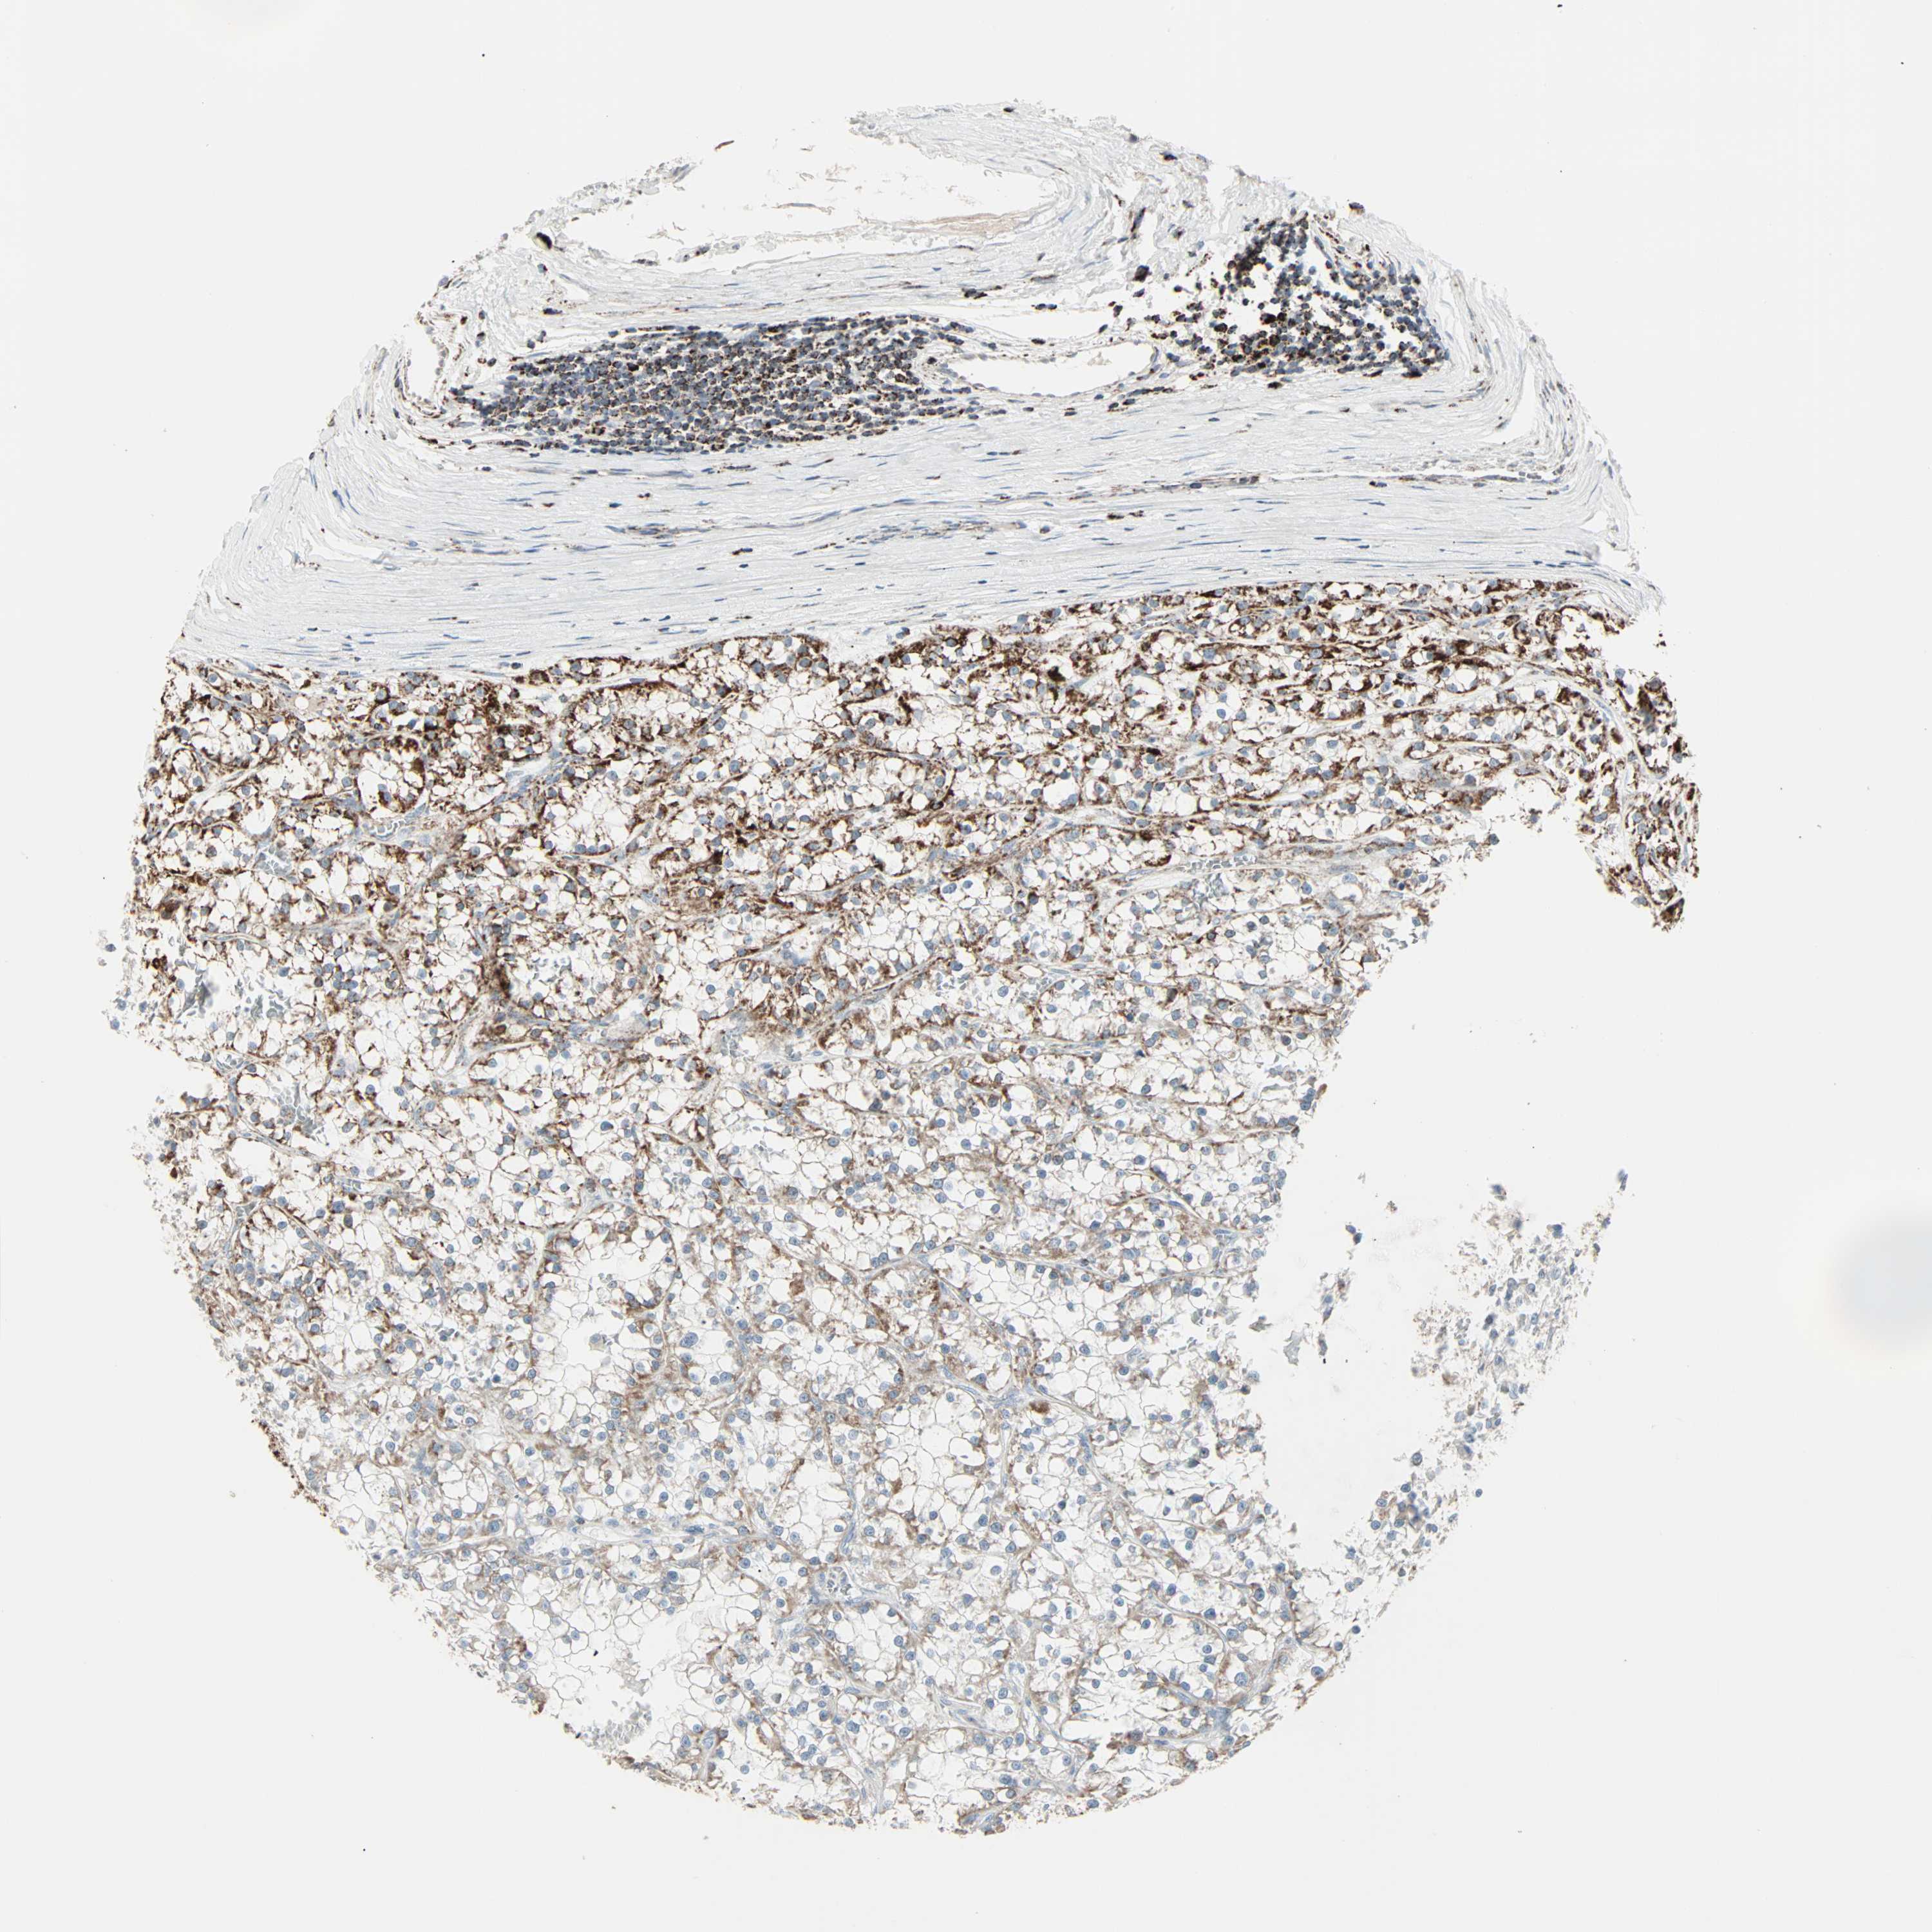

CANCER RENAL CANCER Show tissue menu

KICH TCGA KIRC TCGA KIRC VALIDATION KIRP TCGA PROTEIN RCC CPTAC PROTEIN EXPRESSION